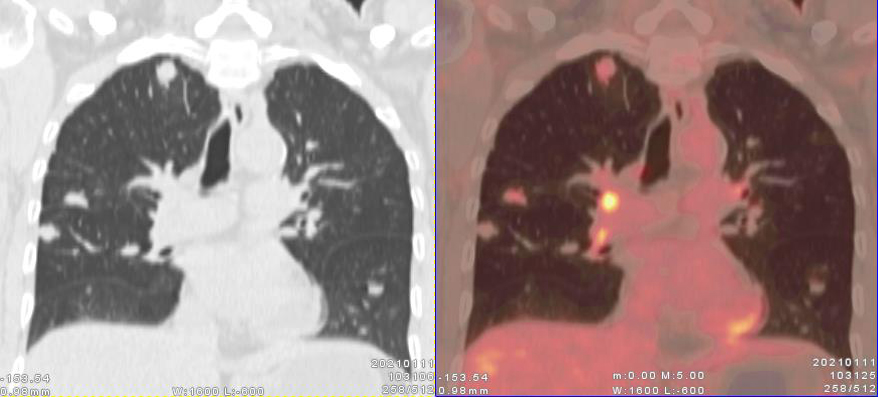

PET/CT影像圖

圖1(左為CT冠狀位圖像、右為冠狀位融合圖像):雙肺多發(fā)散在大小不同的實性結(jié)節(jié),代謝輕度增高。